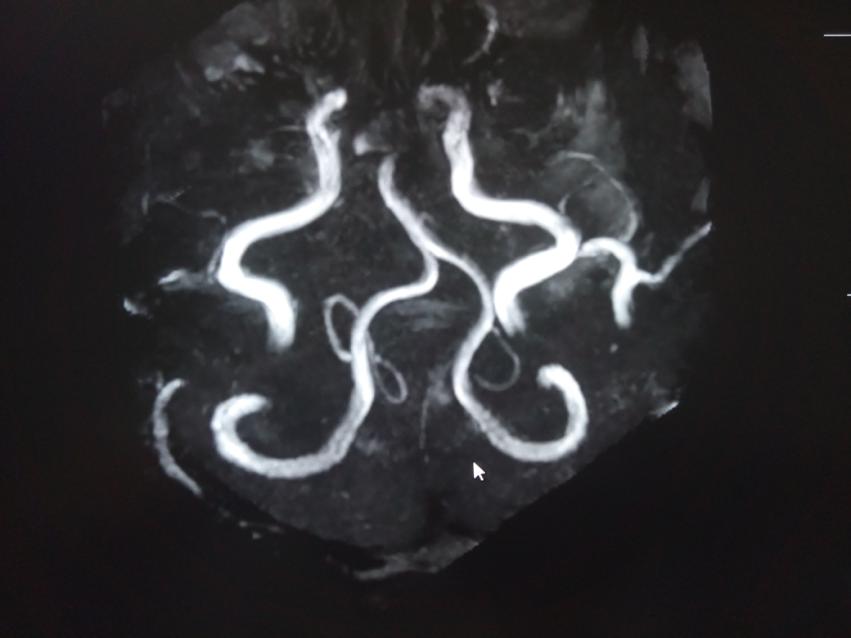

舌咽神經(jīng)MRTA檢查發(fā)現(xiàn)同側(cè)椎動(dòng)脈及小腦后下動(dòng)脈壓迫舌咽及迷走神經(jīng)